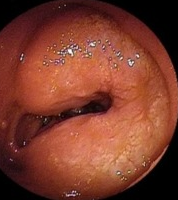

Upper gastrointestinal endoscopy showing a grossly deformed duodenal bulb. A steady trickle of bile was also seen to come from a slit-like orifice on the anterior duodenal wall suggestive of biliary duodenal fistula (green arrow)